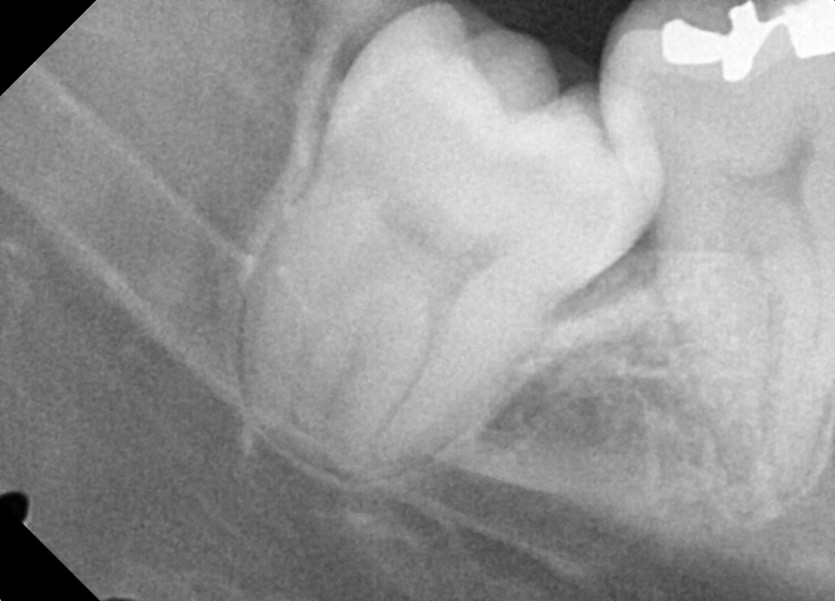

#48 사랑니 발치

구강 외과 전문의가 당일 발치했습니다.